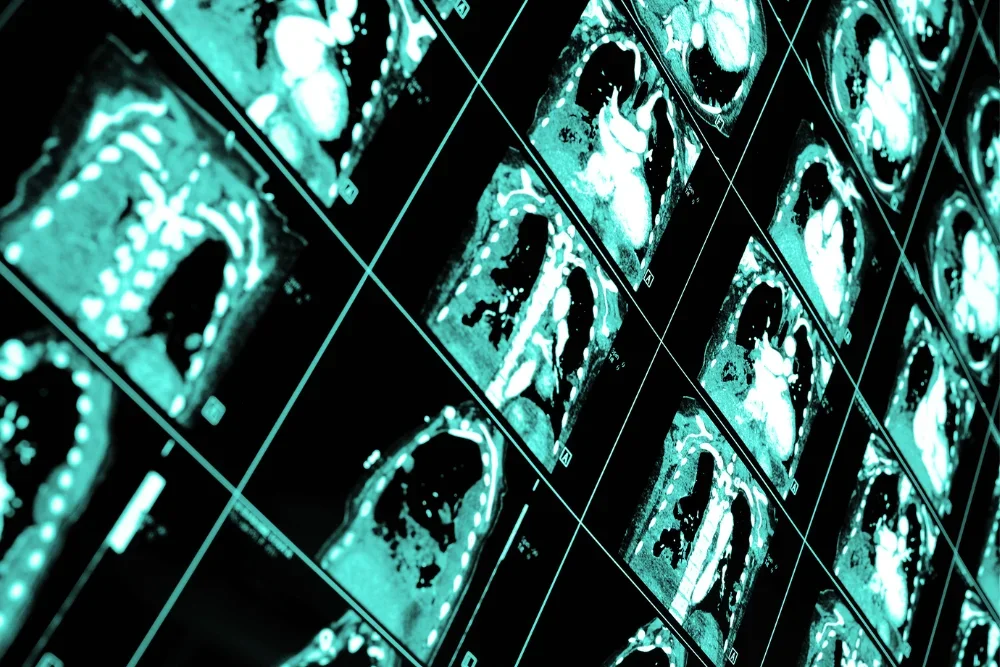

La tomografía de tórax es un procedimiento médico no invasivo que utiliza imágenes de rayos X para obtener una visión detallada de los órganos y estructuras en el área del pecho. Este procedimiento es esencial para evaluar la salud pulmonar y diagnosticar una gran cantidad de padecimientos pulmonares y torácicos.